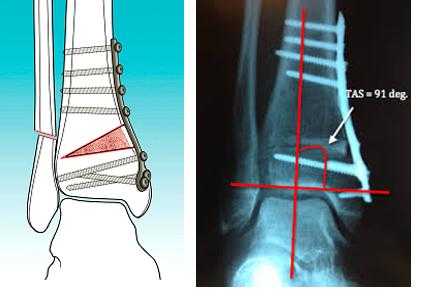

Надлодыжечная остеотомия.

На стадиях 2, 3А, при относительно сохранном объёме движений и поражении внутренних отделов сустава показана вальгизирующая надлодыжечная остеотомия большеберцовой кости.

Данная операция позволяет разгрузить медиальные отделы сустава и перераспределить осевую нагрузку.